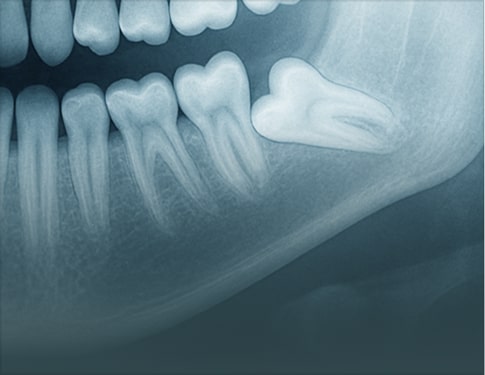

Advanced Report includes annotated images, detailed key findings, and practical clinical recommendations. Choose this option for treatment planning, complex cases, referrals, or when visuals are needed to communicate findings with colleagues or patients and support confident clinical decisions in the final report.